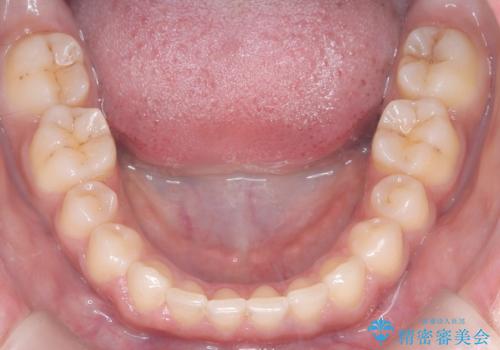

本症例では、非抜歯での治療を選択したため、スペースを確保するためにIPR(歯間削合)を行い、歯列を整えました。オーバージェット(上の前歯と下の前歯の水平的なズレ)は残る結果となりましたが、見た目や機能の改善を重視し、患者様と治療計画を共有しながら進めました。治療中は、歯列全体のバランスと噛み合わせを考慮しつつ、矯正装置の適切な使用を徹底しました。当初の計画通りに治療を完了し、患者様にも満足していただけました。